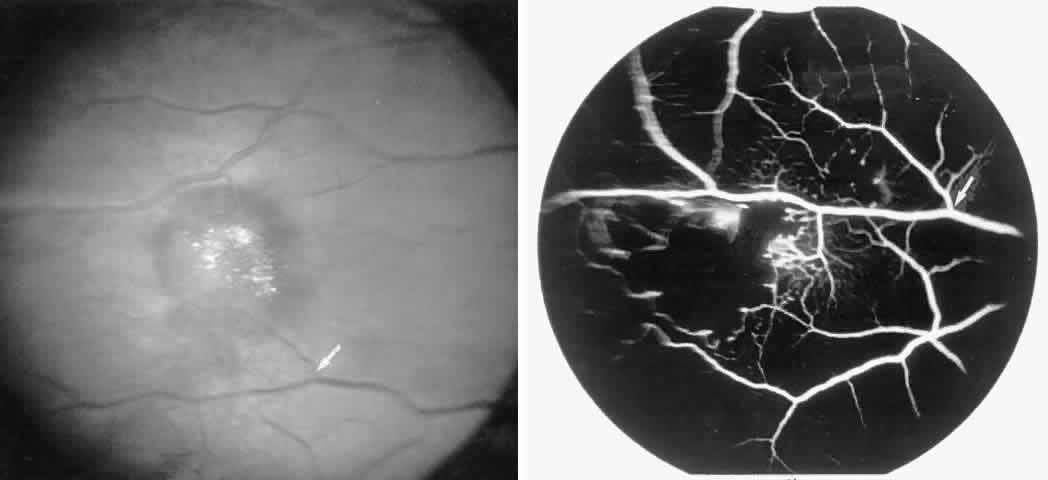

Dilation and tortuosity of the retinal veins was one of the first recognized abnormalities of sickle cell eye disease. Although it is not pathognomonic of sickle cell disease, it reportedly occurs in up to 47% of patients with homozygous sickle cell anemia and 32% of patients with SC disease (Fig. 4).70 The significance of this venous tortuosity is unknown, and the incidence does not appear to be related to age.71

Fig. 4. A. Generalized vascular tortuosity, predominantly venous, in a patient with homozygous sickle cell anemia. B. Localized macular venous tortuosity in a patient with SC disease.